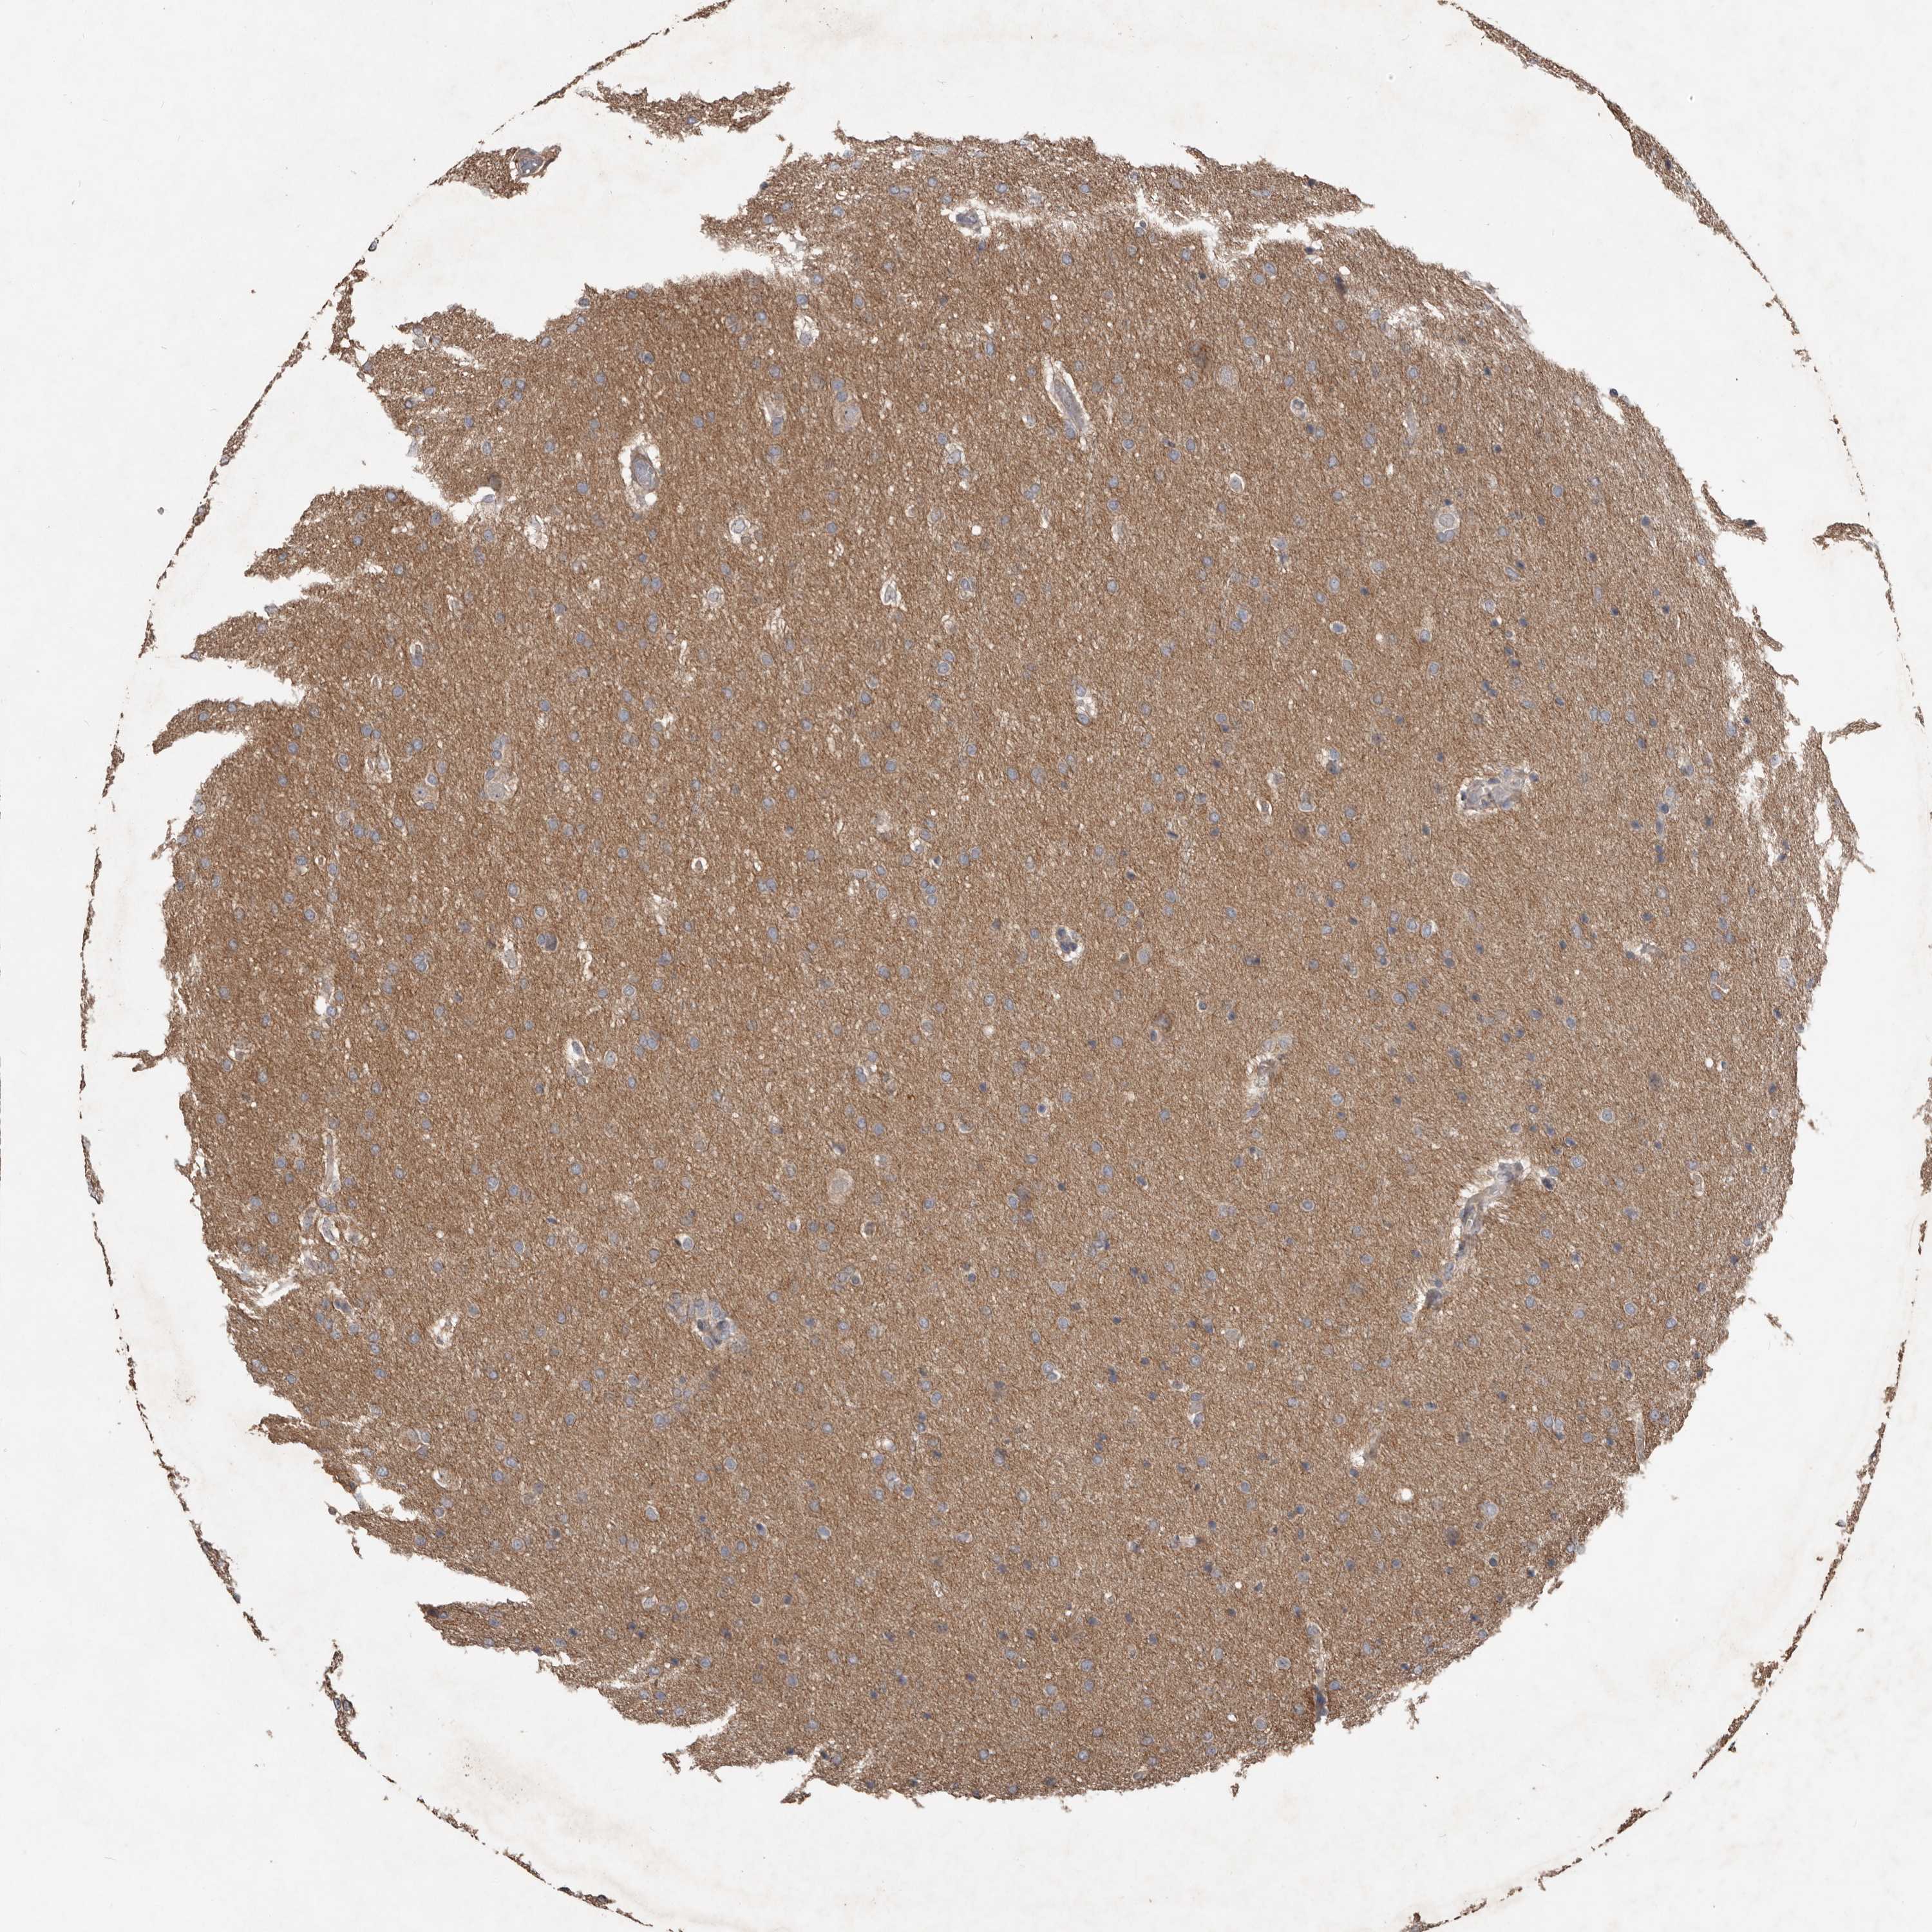

GLIOMA - Protein expressioni

A mouse-over function shows sample information and annotation data. Click on an image to view it in a full screen mode. Samples can be filtered based on level of antibody staining by selecting one or several of the following categories: high, medium, low and not detected. The assay and annotation is described here.

Note that samples used for immunohistochemistry by the Human Protein Atlas do not correspond to samples in the TCGA dataset.

Antibody stainingi

Antibody staining in the annotated cell types in the current human tissue is reported as not detected, low, medium, or high, based on conventional immunohistochemistry profiling in selected tissues. This score is based on the combination of the staining intensity and fraction of stained cells.

Each image is clickable and will lead to virtual microscopy that enables deeper exploration of all samples and also displays staining intensity scores, fraction scores and subcellular localization as well as patient and tissue information for each sample.

Antibody HPA010866

Staining

High

Medium

Low

Not detected

Intensity

Strong

Moderate

Weak

Negative

Quantity

>75%

75%-25%

<25%

None

Location

Nuclear

Cytoplasmic/membranous

Cytoplasmic/membranous,nuclear

Glioma, malignant, High grade

Glioma, malignant, Low grade

Glioblastoma, NOS